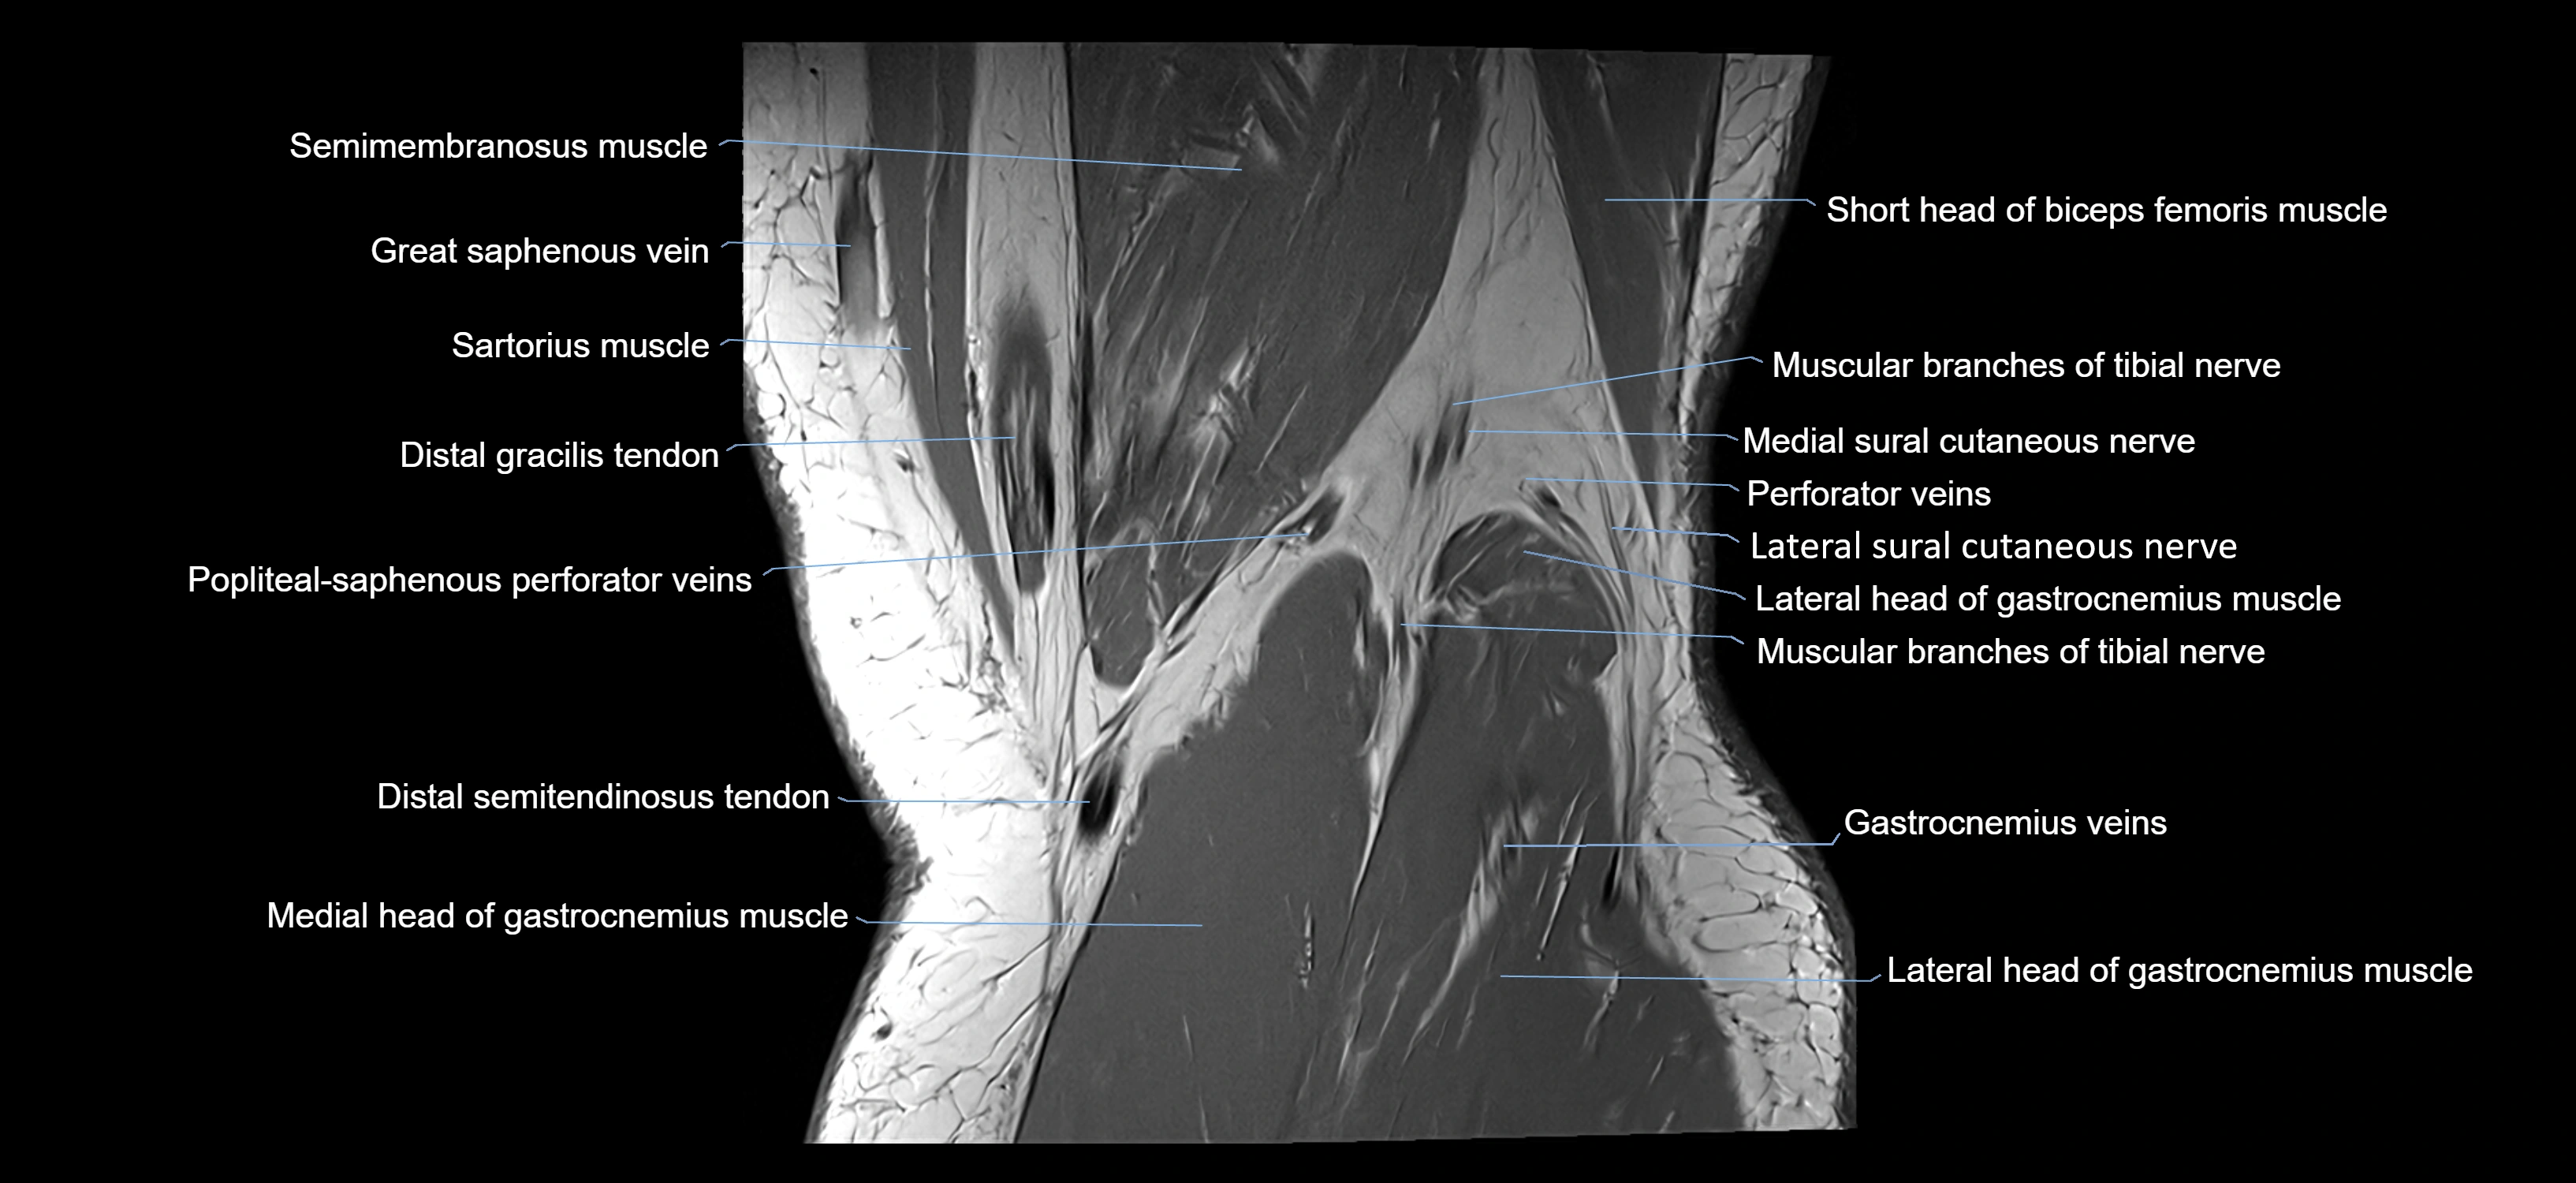

- Distal semitendinosus tendon

- Gracilis tendon (Distal)

- Lateral head of gastrocnemius muscle

- Lateral sural cutaneous nerve

- Medial head of gastrocnemius muscle

- Medial sural cutaneous nerve

- Muscular branches of tibial nerve

- Popliteal–Saphenous perforating veins

- Sartorius muscle

- Semimembranosus muscle

- Small saphenous vein